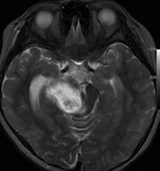

放射線治療13週目

右はガドリニウム増強です。ステロイドとグリセオールの点滴では制御できませんでした。悪性神経膠腫の病名で保険適応があるアバスチン(ベバシズマブ 10mg / kg)の投与を開始しました。

アバスチン投与後15日目

たった2週間で劇的な改善が見られました。失語症と片麻痺や認知機能も改善しました。

4回目のアバスチン投与後

アバスチンをどれだけ続ければいいのかははっきりしていません。2週間おきに6コースまでの投与が基本かもしれません。

この画像を見ると,放射線とテモダールの治療が有効であったのかなと思います。